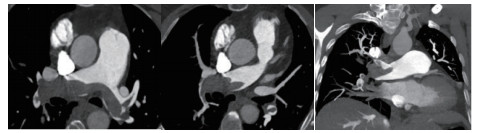

1 经典的挽救性溶栓治疗策略可能带给医生更多的是被动和难度例1 男性,28岁,体质量90 kg。主诉“胸闷、憋气1周加重1 d”。既往:体健;喜久坐(平均10~15 h/d);否认手术史、外伤史;入院查体:神志清楚,体温36.8℃,血压128/80 mmHg(1 mmHg=0.133 kPa),脉搏120次/min,呼吸26次/min,脉氧饱和度96%(安静,空气氧),未见明显乏氧征。双肺呼吸音清,未闻及干湿性啰音。心率120次/min,心律齐,P2 > A2,心界无扩大,无杂音。腹软,无压痛,肠鸣音正常,双下肢无浮肿。神经系统查体未见异常。血气分析(空气氧)提示pH 7.514,PaCO2 27.2 mmHg,PaO2 67.1 mmHg,SaO2 95.0%;D-Dimer:3 035 ng/mL,FDP 33.08 μg/mL,FBG 4.520 g/L;PLT 179.0 G/L,TNI 0.08 ng/mL,BNP 882.00 pg/mL;ALT 38 U/L,AST 17 U/L,CREA 82.6 μmol/L,血Na+、K+、Cl-正常范围;超声心动图(Ultrasonic Cardiogram,UCG)提示:右心增大,肺动脉主干及右肺动脉增宽,肺动脉主干32 mm,三尖瓣反流(重度),反流面积8.6 cm2,TI法估计SPAP为67 mmHg、左室舒末内径50 mm、左室E/A:45/38 cm/s, 左室壁厚度及运动正常,未见节段性室壁运动障碍;双下肢静脉超声提示左侧股静脉血栓形成可能(完全型)。心电图(图 1所示)提示窦性心动过速;肺动脉增强CT(Computed tomographic pulmonary angiography, CTPA)提示双肺主干明确充盈缺损(图 2所示)。入院诊断:急性肺血栓栓塞症(中高危)。入院后给予抗凝治疗(依诺肝素钠90 mg,皮下注射,1次/12 h)重叠华法令治疗的第4天D-Dimer升至47 482 ng/mL,第6天2 411 ng/mL。第7天常规复查双下肢超声未见新增血栓形成,复查UCG(当天INR 2.25)提示右心房漂浮血栓,并随心脏蠕动明显(图 3所示)。在准备胸外科手术取栓的过程中出现血压下降至70/40 mmHg,脉氧饱和度降至45%,立即给予气管插管并系统溶栓治疗(r-tPA 100 mg于2 h输注),溶栓治疗1.5 h患者血压逐渐回升并趋于稳定、溶栓治疗3 h自主呼吸开始恢复,于插管3天后(住院第10天)拔出气管插管,成功撤离呼吸机。溶栓过程中曾经出现消化道、气道出血,血红蛋白下降1.9 g/dL,未予输血治疗。溶栓后复查CTPA提示双肺主干血栓负荷明显减少,远段血液灌注明显增加(图 4所示)。

| 图 2 入院时CTPA提示双肺主干明确充盈缺损 |

| 图 4 溶栓后的CTPA肺动脉主干血栓负荷明显减少、远段血液灌注明显增加 |